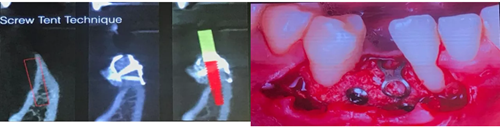

(一)針對(duì)下頜前牙區(qū)牙槽嵴嚴(yán)重骨吸收的患者,教授提出可以應(yīng)用植骨釘加不可吸收膜帳篷技術(shù)進(jìn)行水平向的骨增量: